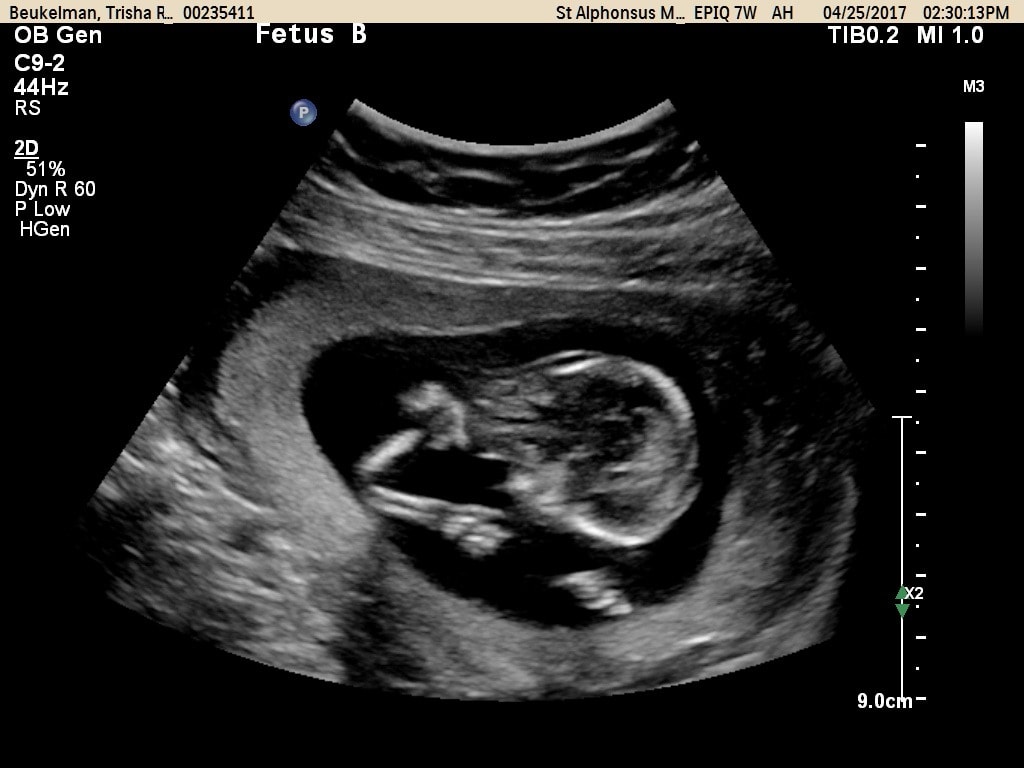

- Ultrasound Photos at 13 Weeks Pregnant With Twin

Ultrasound Photos at 13 Weeks Pregnant With Twin